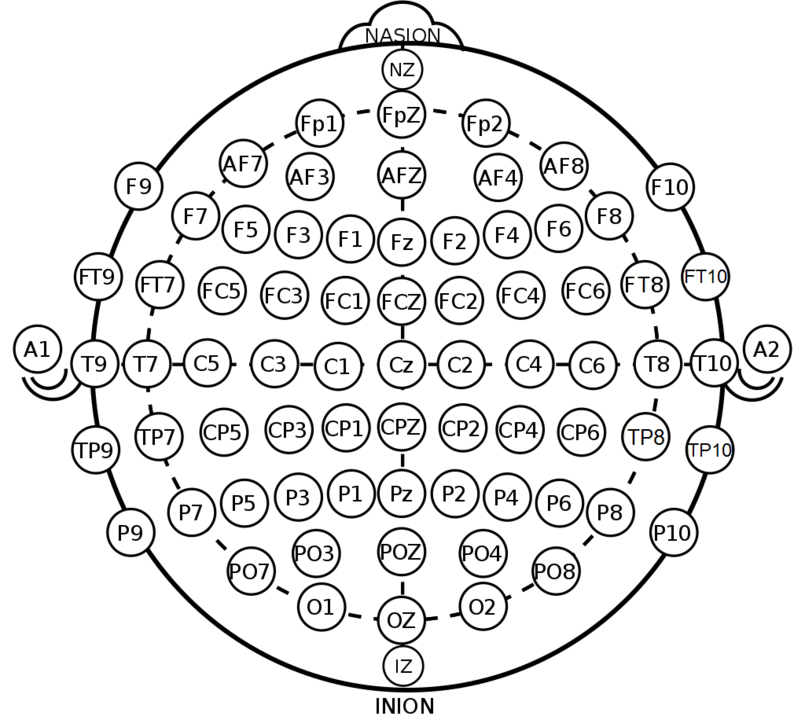

Positionen zur EEG Ableitung

|

|

|---|---|

|